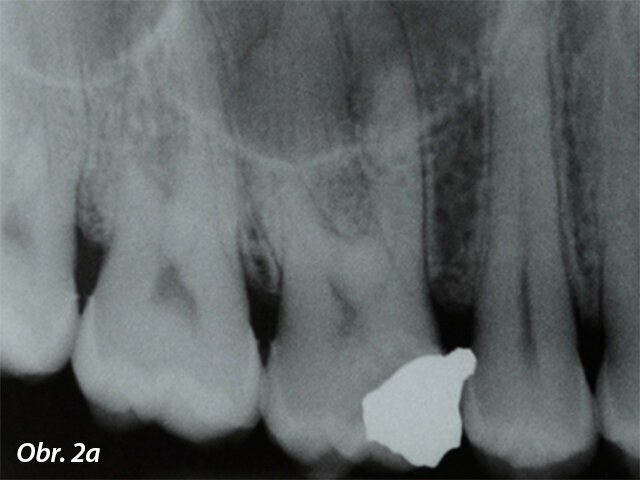

In vitro a ex vivo studie ukázaly přítomnost bakterií v dentinových tubulech a cementu i po endodontickém ošetření, což zdůrazňuje, že cíl absolutní dezinfekce kanálku není pravděpodobně dosažitelný pouhým čištěním a opracováním.Plnění opracovaného kořenového kanálku je následným krokem v endodontické terapii a slouží jako prevence bakteriální reinfekce zubu a periapexu. Většina obturačních systémů v endodontické terapii je složena ze základního materiálu a sealeru. Sealer by měl nejen vyplnit mezery mezi základním materiálem a stěnou kořenového kanálku, ale také povrchové nerovnosti systému kořenových kanálků (jako jsou laterální kanálky a isthmy), aby bylo dosaženo pevného utěsnění (obr. 2a, b).K překonání problému bakteriální persistence v systému kořenových kanálků byly postupně vyvíjeny a uváděny na trh materiály s antibakteriálními vlastnostmi. Antibakteriální povaha sealeru je cenná kvůli vyššímu procentu fakultativních anaerobů v případech selhání léčby kořenových kanálků. Objevilo se několik sealerů na bázi pryskyřic a MTA, u kterých výrobci tvrdili, že mají schopnost zničit bakterie ponechané v dentinu kořenových kanálků, avšak literatura ukázala, že antimikrobiální sealery (především sealery na bázi pryskyřice) jsou efektivnější, když jsou čerstvě namíchány, a jejich aktivita se snižuje po ztuhnutí,a tedy se na ně nelze spoléhat v prevenci reinfekce v průběhu delšího období.

Úspěšná terapie je, když jsou plnicí materiály schopny pevně utěsnit prostor kořenových kanálků, a to i v případě více výstupů